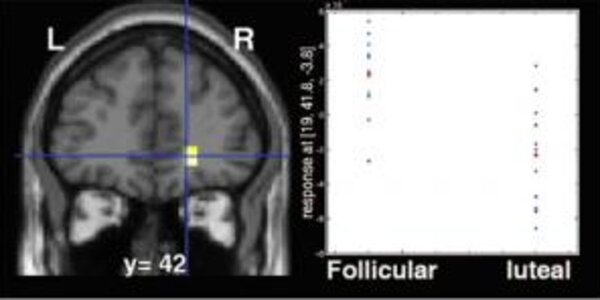

Brain's Reward Circuit Activity Ebbs And Flows With A Woman's Hormonal Cycle

Fluctuations in sex hormone levels during women's menstrual cycles affect the responsiveness of their brains' reward circuitry, an imaging study at the National Institute of Mental Health (NIMH), a component of the National Institutes of Health (NIH), has revealed. While women were winning rewards, their circuitry was more active if they were in a menstrual phase preceding ovulation and dominated by estrogen, compared to a phase when estrogen and progesterone are present. Brain activity in the orbitofrontal cortex (yellow), part of the brain's reward system, was increased during women's pre…

Influence Of The Menstrual Cycle On The Female Brain

What influence does the variation in estrogen level have on the activation of the female brain? Using functional Magnetic Resonance Imaging, Jean-Claude Dreher, a researcher at the Cognitive Neuroscience Center (CNRS/Université Lyon 1), in collaboration with an American team from the National Institute of Mental Health (Bethesda, Maryland) directed by Karen Berman, has identified, for the first time, the neural networks involved in processing reward-related functions modulated by female gonadal steroid hormones. This result, which was published online on January 29, 2007 on the PNAS website…